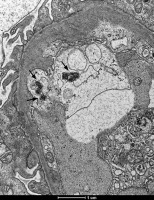

Fig. 1

Tubuloreticular inclusions (TRIs) observed in monocytes (A) and macrophages (B) in renal biopsy samples collected from patients with juvenile systemic lupus erythematosus (jSLE). TRIs are indicated with arrows